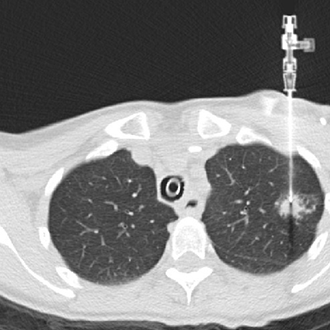

BIOPSY

Biopsy and Drainage

We at Gokul Diagnostic and Scan Centre provide facilities for various radiological interventions under the guidance of CT Scan, XrayFluroscopy and Ultrasonography.

As we have availability of various modalities we choose from CT or Sonography guidance whichever is best suited for the patient under given clinical scenario.

We have a team of dedicated radiologists who are highly trained in doing imaging based interventions.

We have excellent success rates with patient safety being our priority.

We Perform :

1. CT/USG guided biopsies.

2. CT/USG guided drainages.

3. FNAC